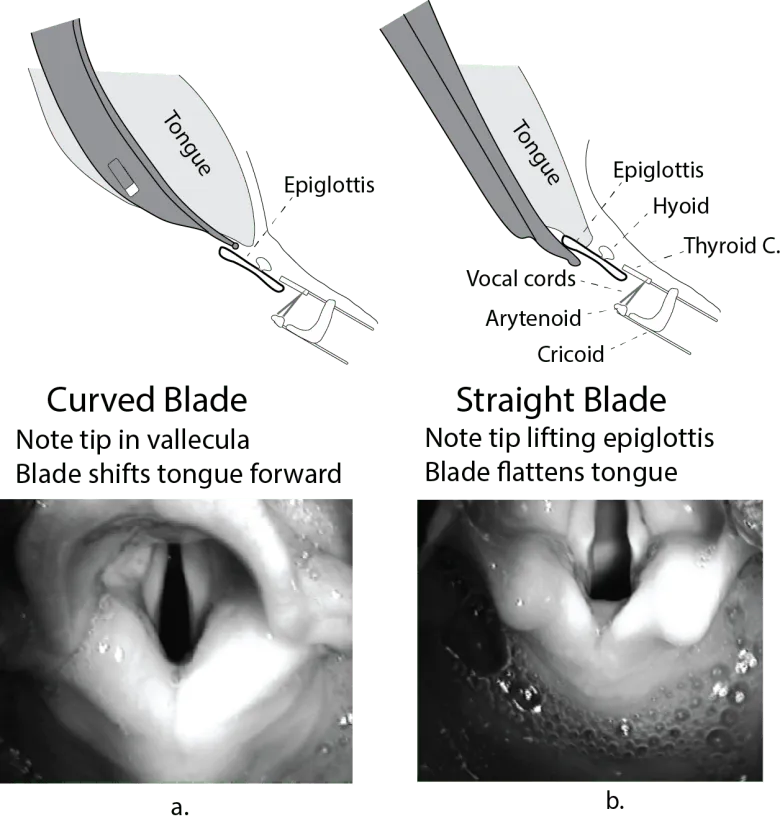

Feature Macintosh (Mac) Miller Shape Curved Straight Tip Placement Vallecula (indirectly lifts epiglottis) Directly lifts epiglottis Adult Sizes 3-4 2-3 Advantages More tongue space Better view in anterior/floppy epiglottis Common Use Adults Infants, difficult anterior airway 📌 Mnemonic Mac in Vallecula Miller Lifts (epiglottis)

⭐ The Macintosh blade is generally preferred in adults, while the Miller blade is often used in infants and patients with a long, floppy epiglottis or an anterior larynx.

- Macintosh blade (curved) fits into the vallecula; Miller blade (straight) directly lifts the epiglottis.